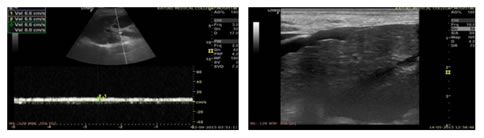

Figure 1: USG Axial image showing Dilated Portal Vein; Figure 2: USG Axial image showing Loss of Respiratory variations in Portal Vein diameter; Figure 3: Colour Doppler showing Flow reversal in Splenic vein; Figure 4: Colour Doppler Axial image: Flow reversal in SMV shown by arrow; Figure 5: USG Axial image showing dampened flow in Portal vein; Figure 6: HRUS image showing Nodular liver surface in cirrhosis

Figure 7: Spectral Doppler USG image: Showing Biphasic flow in Splenic vein; Figure 8: Gray scale and Colour Doppler USG image: Showing Cavernomatous transformation of Portal vein; Figure 9: Gray scale and Colour Doppler USG image; Figure 10: Showing Dilated Coronary vein with Hepatofugal flow; Figure 11: Gray scale and Colour Doppler USG image: Showing GEJ collaterals; Figure 12: Gray scale and Colour Doppler USG image: Showing Lienorenal collaterals; Figure 13: Gray scale and Colour Doppler USG image: Showing Recannalised Paraumbilical vein with hepatofugal flow; Figure 14: Colour Doppler USG image: Showing Absent Colour flow in Portal vein due to Thrombosis